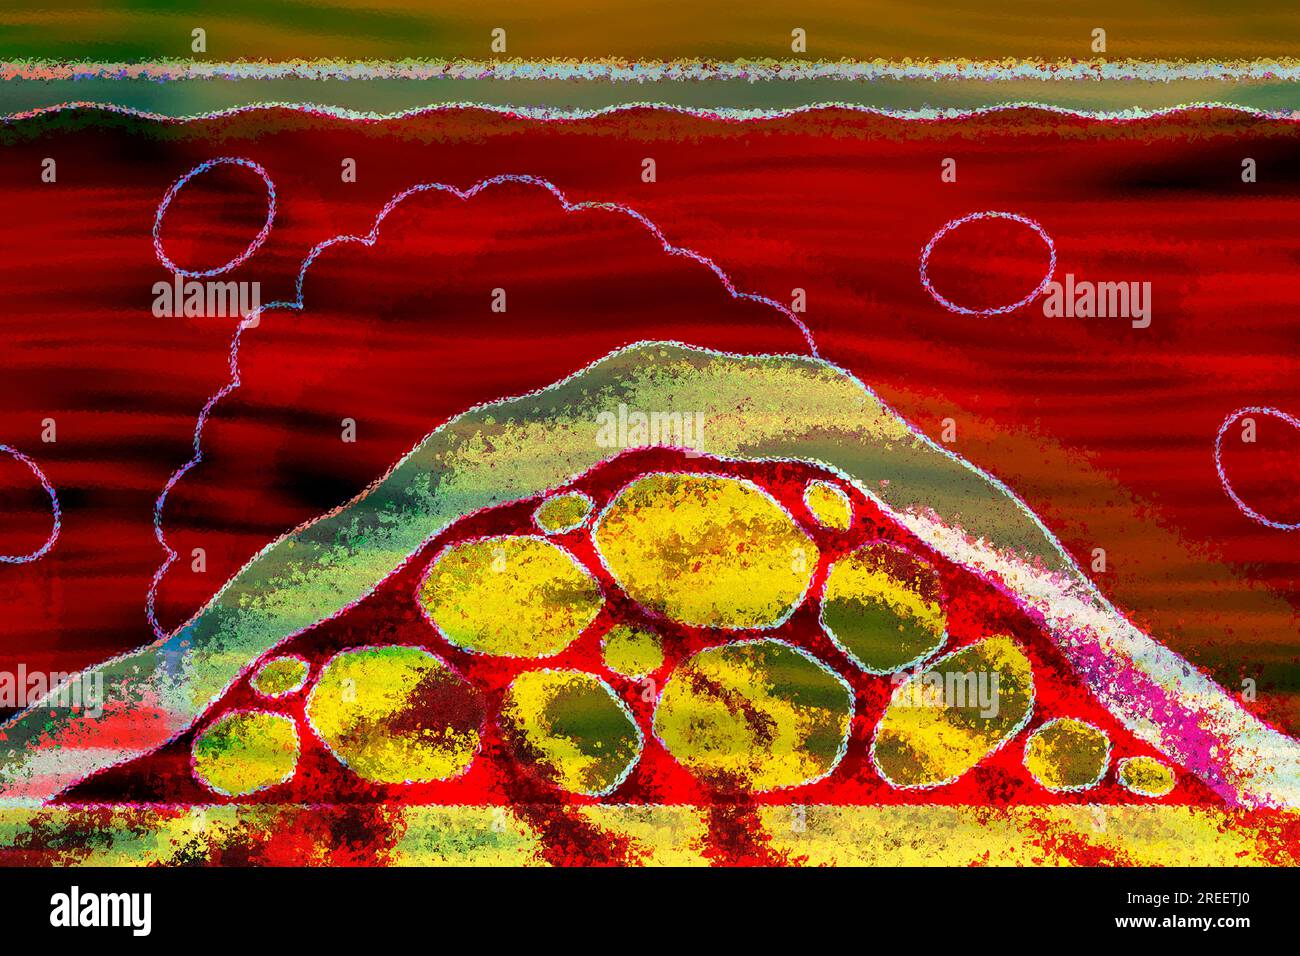

Arteriosclerosis is a common vascular disease in which the arteries become narrowed and hardened by deposits such as fats Stock Photohttps://www.alamy.com/image-license-details/?v=1https://www.alamy.com/arteriosclerosis-is-a-common-vascular-disease-in-which-the-arteries-become-narrowed-and-hardened-by-deposits-such-as-fats-image559663608.html

Arteriosclerosis is a common vascular disease in which the arteries become narrowed and hardened by deposits such as fats Stock Photohttps://www.alamy.com/image-license-details/?v=1https://www.alamy.com/arteriosclerosis-is-a-common-vascular-disease-in-which-the-arteries-become-narrowed-and-hardened-by-deposits-such-as-fats-image559663608.htmlRF2REETJ0–Arteriosclerosis is a common vascular disease in which the arteries become narrowed and hardened by deposits such as fats